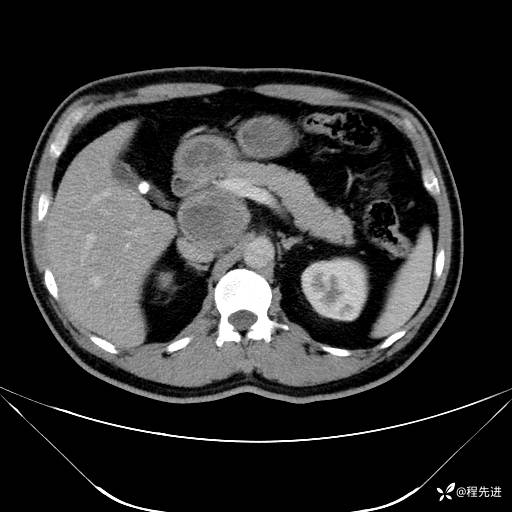

【腹盆】特别精彩病例|发现腹膜后肿物1月余

主诉:发现腹膜后肿物1月余

现病史:患者1月余前查体,行超声检查提示:后腹膜囊实性肿块;慢性胆囊炎伴胆囊内结石;无腹痛腹胀,不伴腹泻发热等;偶感腰背部酸痛。

CT平扫+增强: